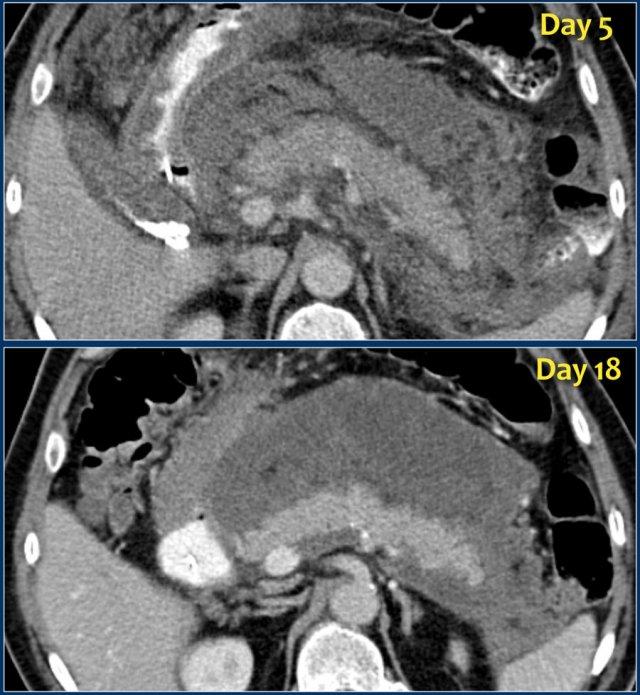

Các dấu hiệu bao gồm:

- Tụy ngấm thuốc bình thường toàn bộ.

- Các ổ dịch quanh tụy lan rộng, có tỷ trọng dạng lỏng và không lỏng trên CT.

- Có ít nhất hai ổ dịch, nhưng không có hoại tử nhu mô tụy (CTSI: 4).

- Vào ngày thứ 18, các ổ dịch quanh tụy mở rộng và xuất hiện thành không hoàn toàn.

Vào ngày thứ 5, ổ dịch này có thể được chẩn đoán là ổ hoại tử cấp tính có khả năng cao.

Vào ngày thứ 18, thành chưa hoàn toàn, nhưng có thể dự đoán rằng trong vài ngày tới đây sẽ trở thành ổ hoại tử được bao bọc với thành hoàn chỉnh.

Khi các ổ dịch quanh tụy tồn tại dai dẳng hoặc tăng kích thước, thường là do sự hiện diện của hoại tử mỡ.

Do mỡ không ngấm thuốc trên CT, việc chẩn đoán hoại tử mỡ có thể gặp khó khăn.

Hoại tử có thể được chẩn đoán bằng MRI, tuy nhiên chỉ nên thực hiện khi có ý nghĩa lâm sàng trực tiếp.